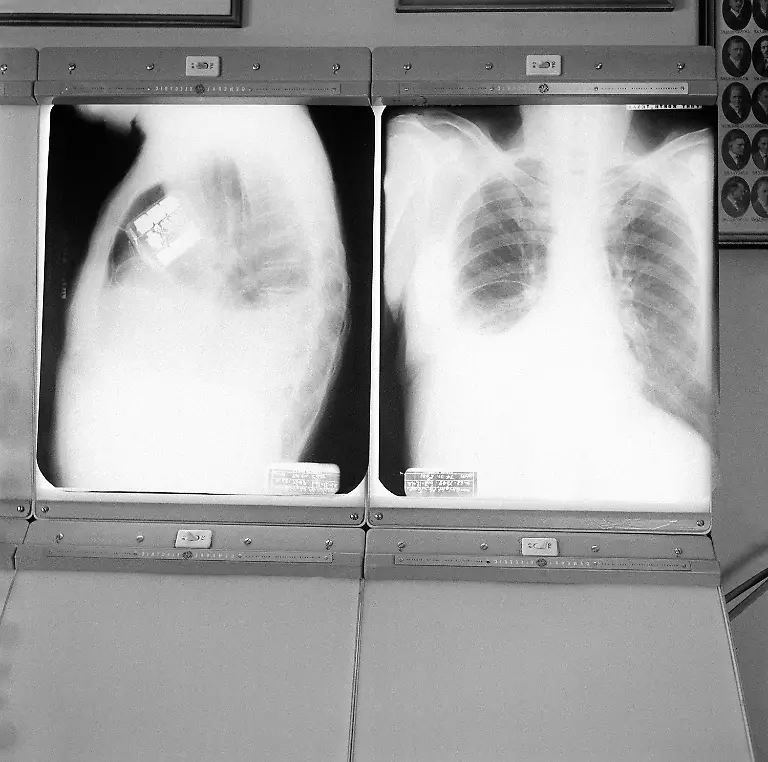

Am 8. Oktober 1958 wird erstmals ein Herzschrittmacher in einen menschlichen Körper eingesetzt. Seitdem helfen die kleinen Kisten dabei, das Herz wieder im richtigen Takt schlagen zu lassen - und retten damit Leben.